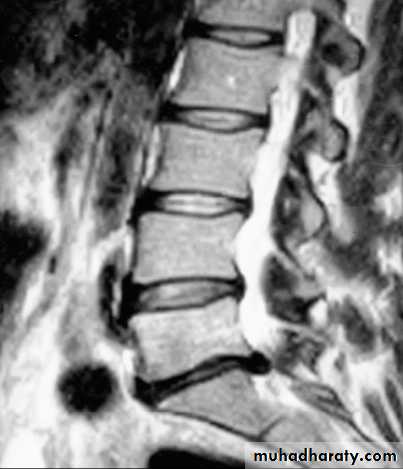

Plain X-rays of the lumbar spine are of little value in the diagnosis of lumbar disc disease, although they may show other conditions such as malignant infiltration of a vertebral body. CT, especially using spiral scanning techniques, can provide helpful images of the disc protrusion and/or narrowing of the exit foramina. MRI is the investigation of choice if available, since soft tissues are well imaged.L5–SI disc herniationto the left, displacing the SI nerve root